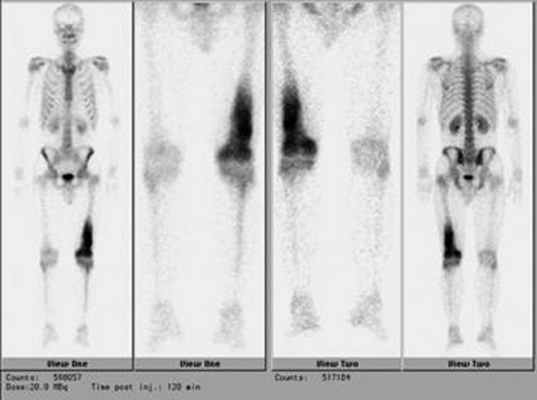

Планарная сцинтиграфия дает возможность определить распространенность опухоли по длине кости, а также выявляет отдаленные метастазы остеосаркомы в скелете (рис. 5).

Рис. 5. Радиоизотопное исследование скелета при саркомах костей

- Остеосцинтиграфия – исследование костного скелета с контрастным веществом для лучшей визуализации опухоли;